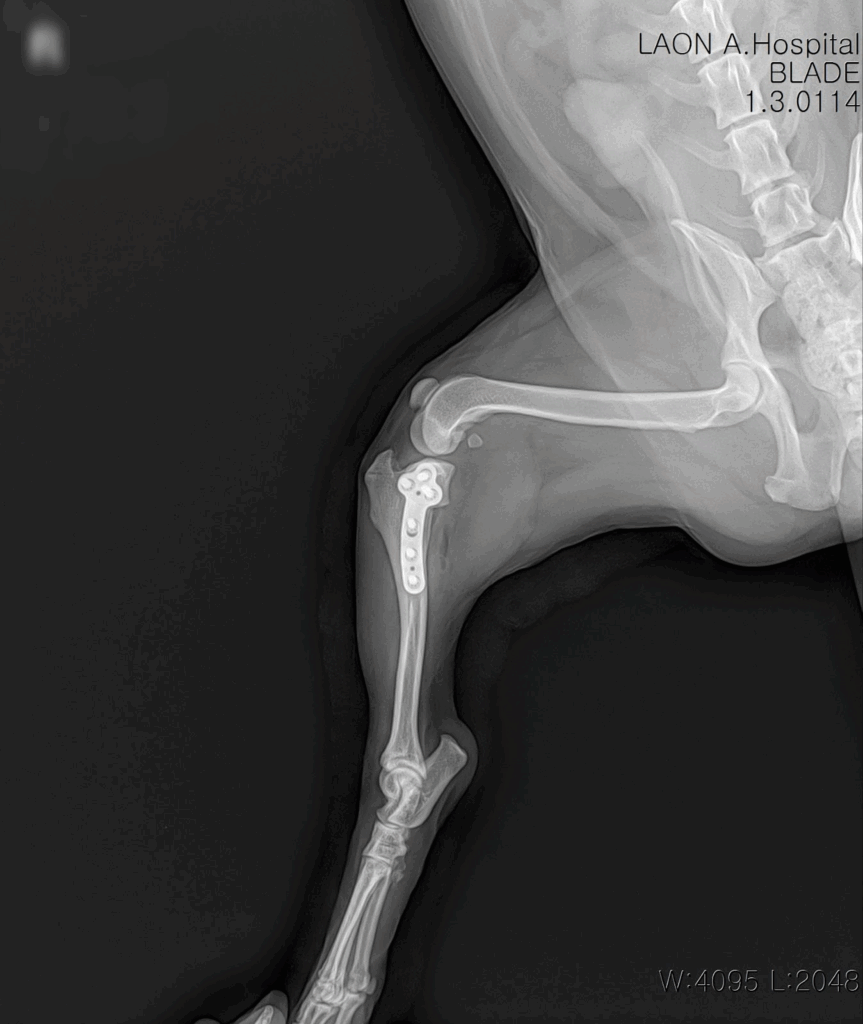

수술은 마취 안정 하에 무사히 마무리되었고, 절개 부위 봉합 후 감염 방지와 회복을 위한 집중 치료가 이어졌습니다.

수술 후 방사선사진 / 출처: 라온동물메디컬센터

수술 후 약 1주간 입원 치료를 진행하며 초기 재활 프로그램도 함께 시작했습니다. 재활 초반에는 통증 조절과 부기 완화에 중점을 두고, 점차 체중 부하 훈련 및 관절 운동 범위 회복을 도왔습니다. 이 사례에서 알 수 있듯, 대형견은 단 한 번의 무리한 동작으로도 파열이 발생할 수 있으므로 사전 예방이 무엇보다 중요합니다.